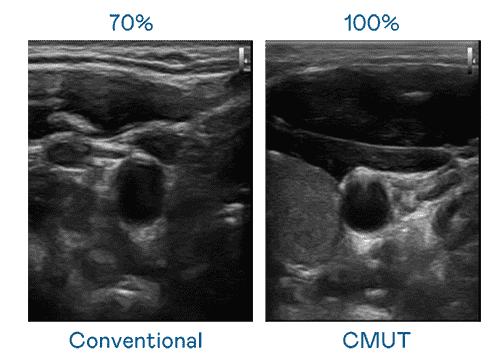

CMUT 技术是一种用电容式微机电元件来产生超音波讯号的技术。。。。与传统 PZT 压电式技术相比,,,,CMUT 频宽增加 30%,,,,更宽频的超音波讯号让影像解析度大幅提升,,,是实现高影像品质医疗超音波扫描、、、、促进精准医疗发展的关键技术。。

大频宽带来超清晰影像

超音波影像的解析度高低,,,首先取决于探头能发出的讯号频宽。。杏悦2 CMUT 可提供高清晰的超音波讯号,,,提供高频宽、、、高灵敏度、、影像纹理细节更高的超音波影像,,协助医护人员缩短影像判读时间及利用精准的医疗影像进行诊断。。